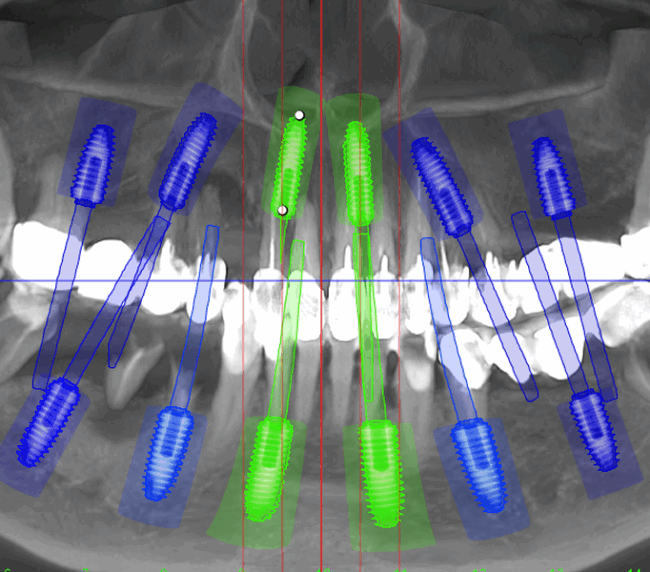

- Investigație imagistică completă, ideal CBCT (computer tomografie);

- Planificare computerizată a intervenției, inclusiv realizarea și utilizarea ghidului chirurgical, dacă este necesar;